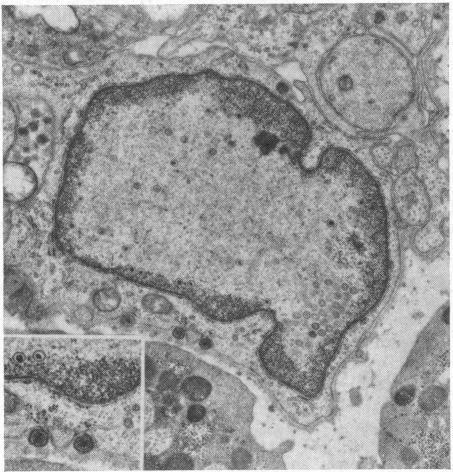

医务人员会议。单纯疱疹性脑膜炎。

Medical staff conference. Herpes simplex meningoencephalitis.

Calif Med. 1967 Nov;107(5):525-34.